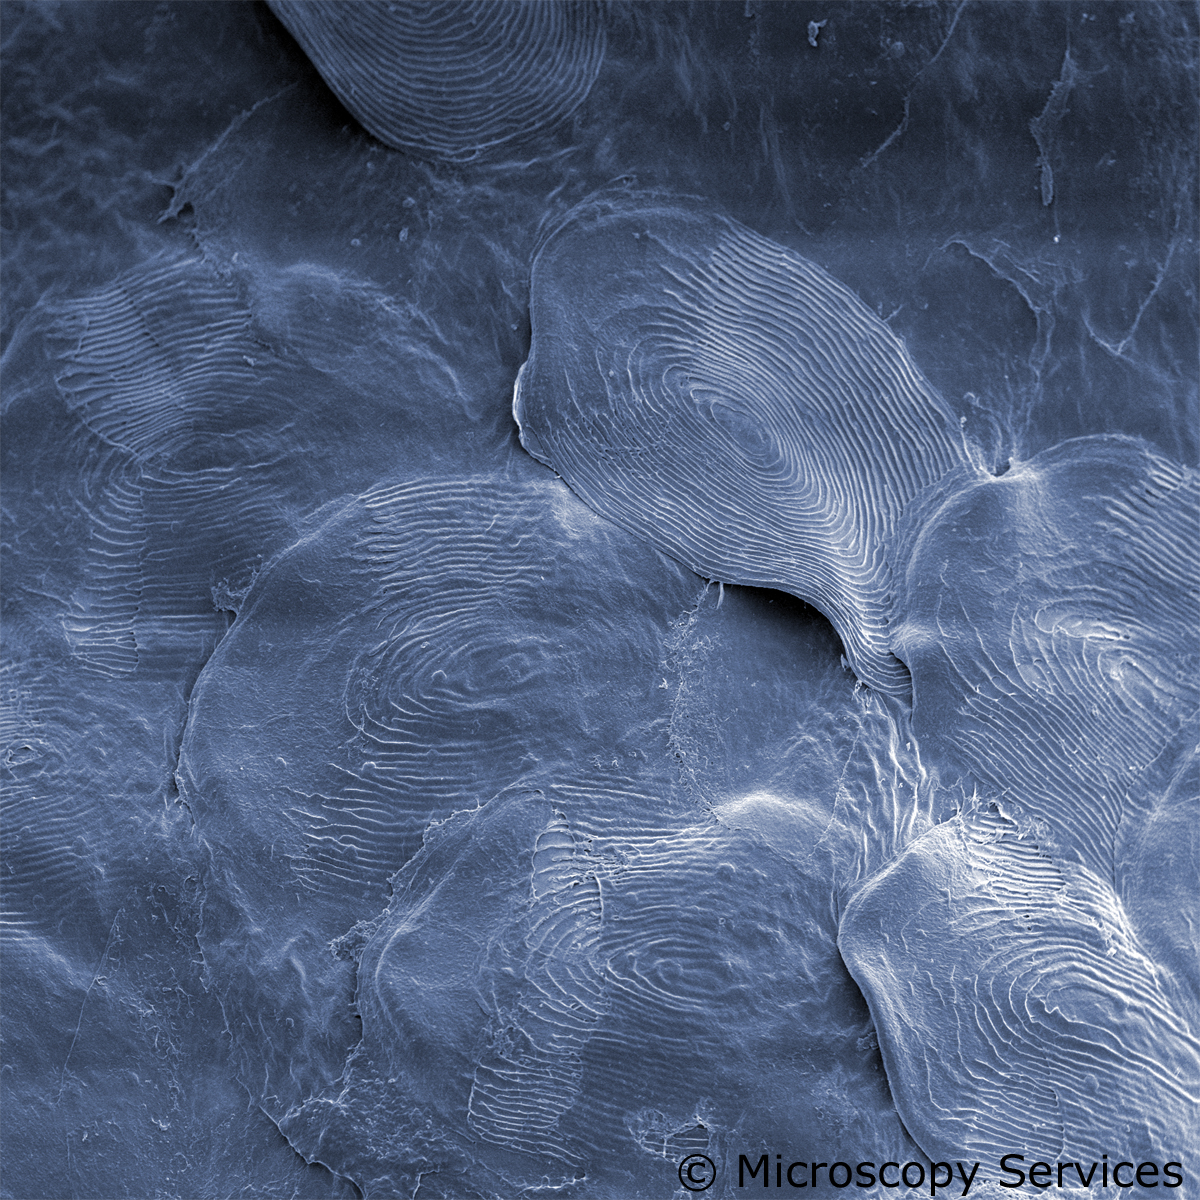

Microscopy Services setzt das patentierte Analyseverfahren Lipbarvis® (Lipid Barrier Visualisation, LBV) ein, um die epidermale Hautbarriere direkt ohne invasive Probenahmen untersuchen zu können.